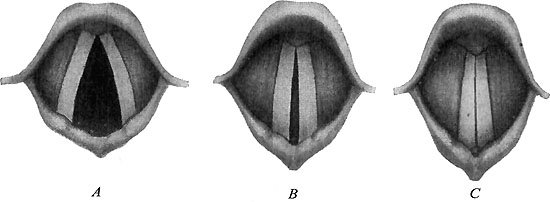

272 The Vocal Cords

This burning quality makes the starches a capital fuel both in the body and out of it. You may have heard of how settlers out on the prairies, who were a long way from a railroad and had no wood or coal, but plenty of corn, would fill their coal scuttles with corn and burn that in their stoves; and a very bright, hot fire it made.